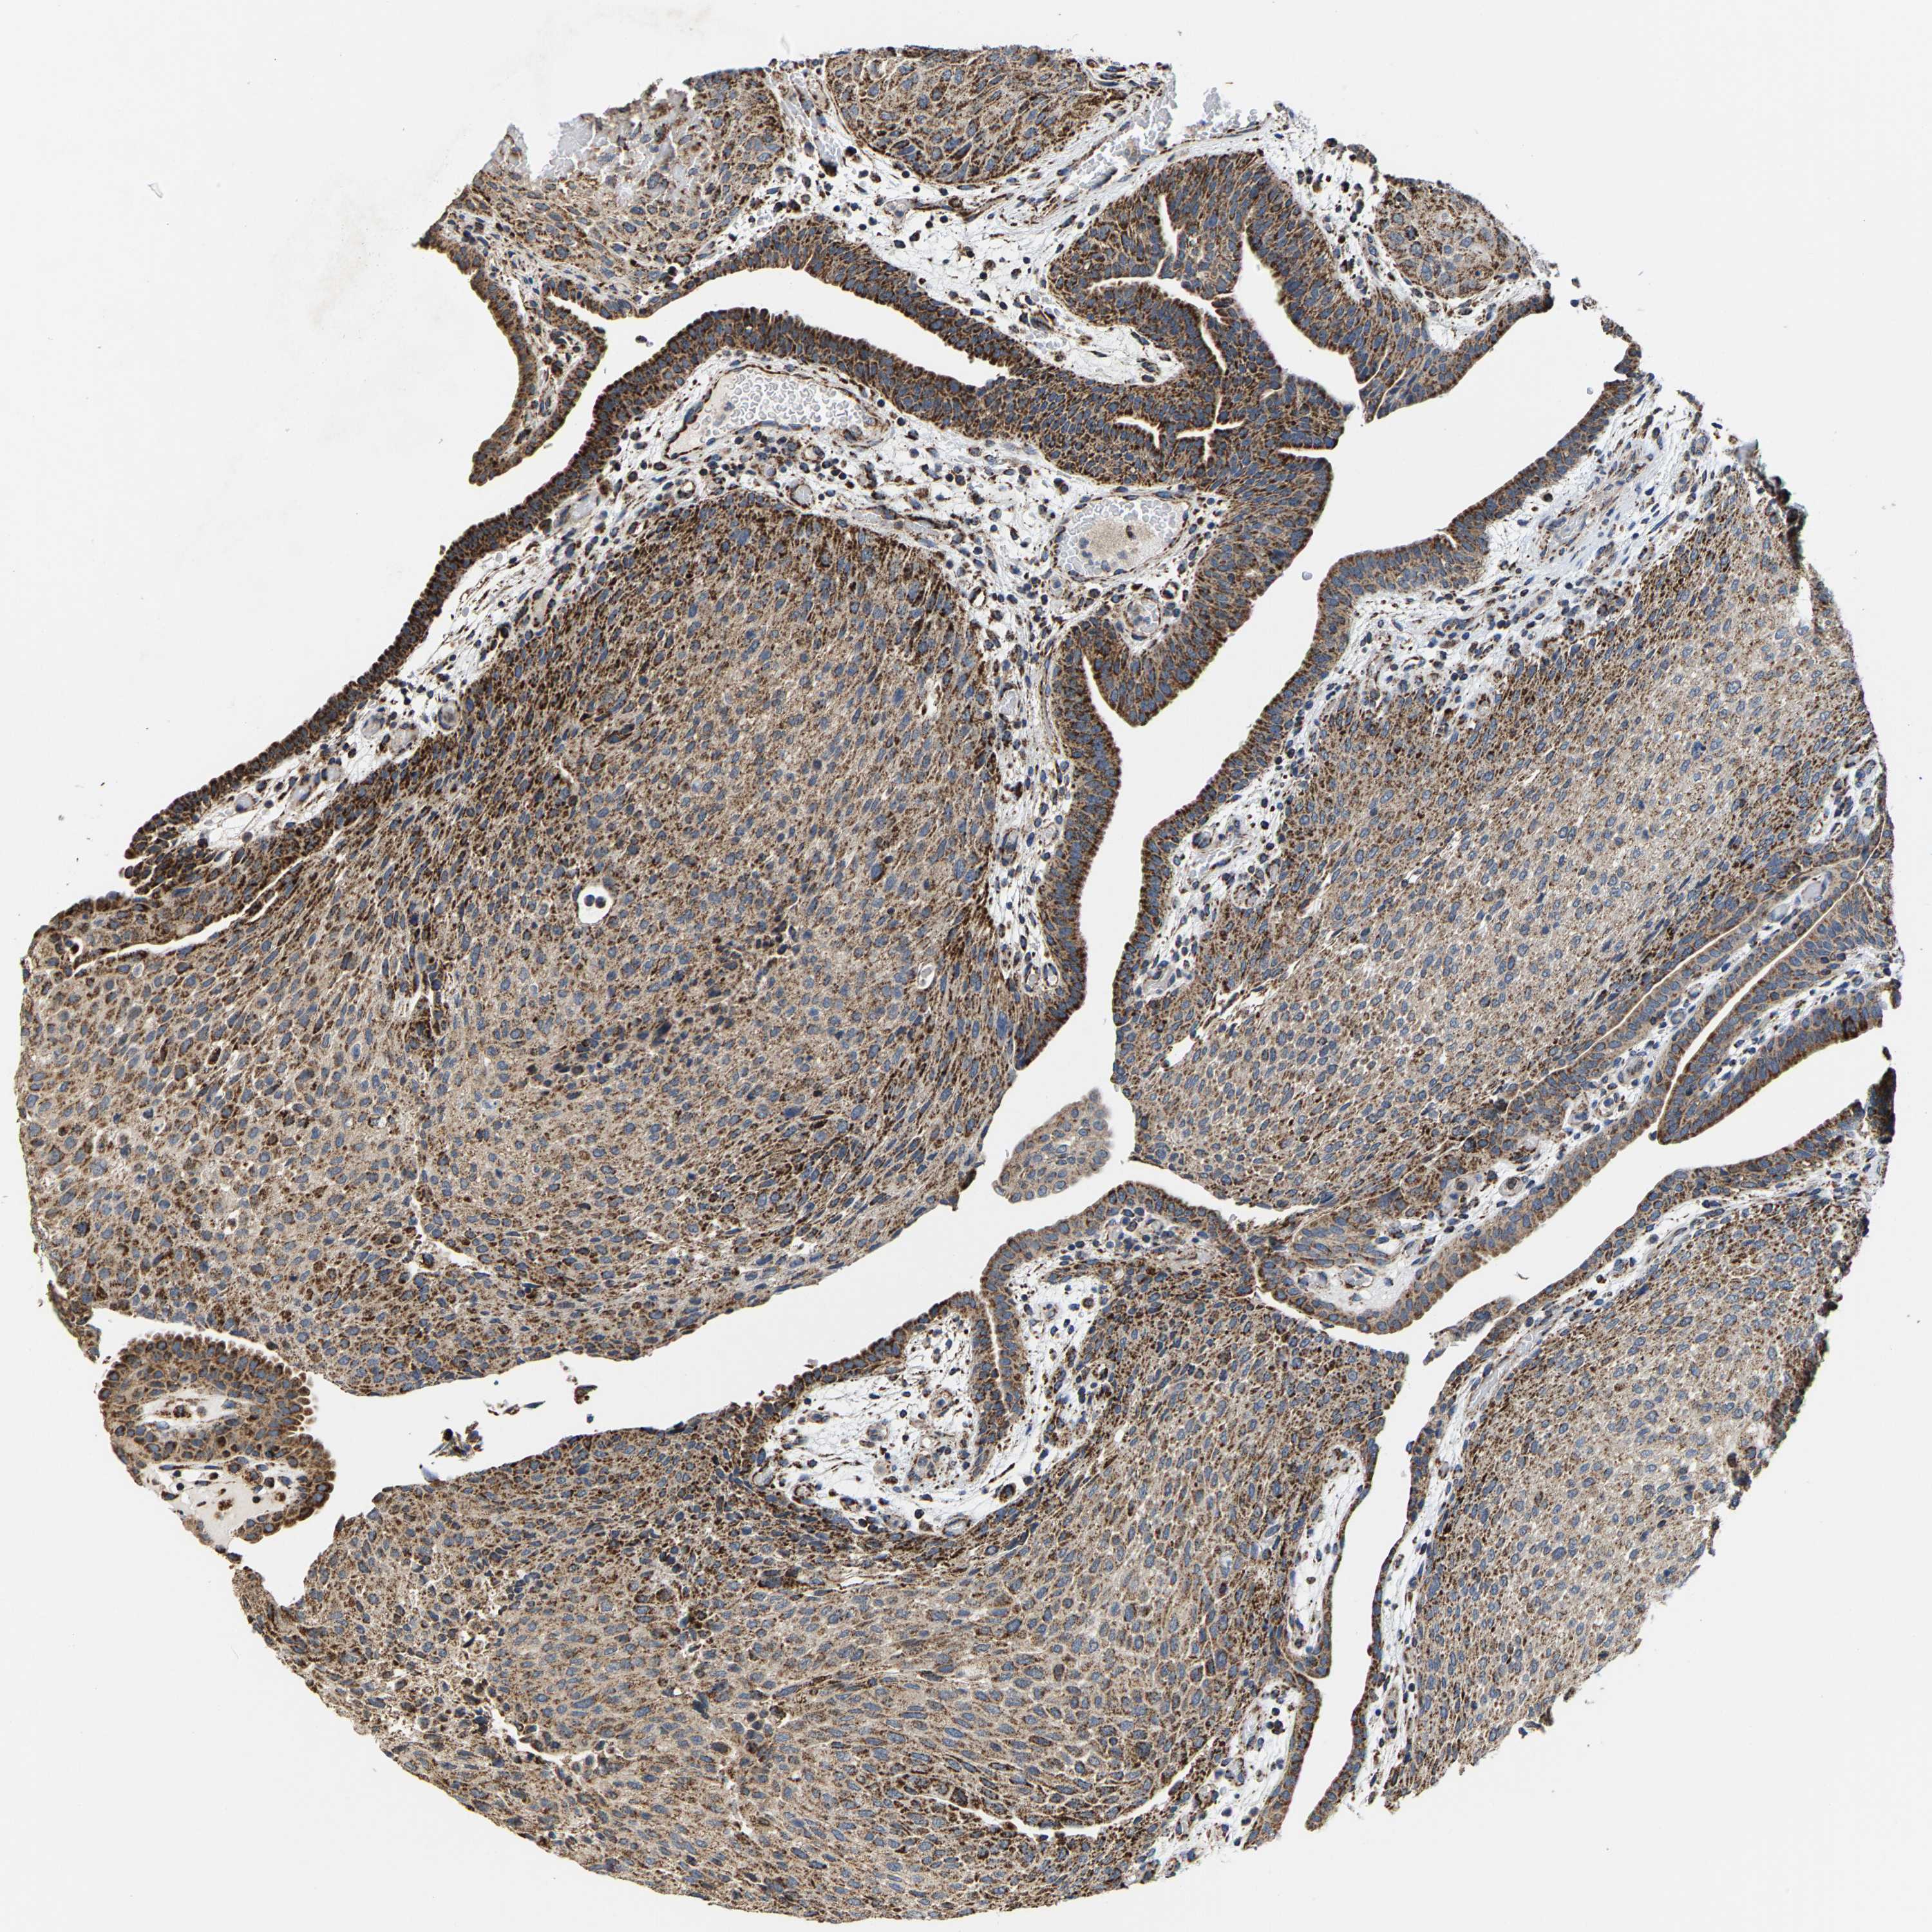

UROTHELIAL CANCER - Protein expressioni

A mouse-over function shows sample information and annotation data. Click on an image to view it in a full screen mode. Samples can be filtered based on level of antibody staining by selecting one or several of the following categories: high, medium, low and not detected. The assay and annotation is described here.

Antibody stainingi

Antibody staining in the annotated cell types in the current human tissue is reported as not detected, low, medium, or high, based on conventional immunohistochemistry profiling in selected tissues. This score is based on the combination of the staining intensity and fraction of stained cells.

Each image is clickable and will lead to virtual microscopy that enables deeper exploration of all samples and also displays staining intensity scores, fraction scores and subcellular localization as well as patient and tissue information for each sample.

Antibody HPA020543

Antibody HPA020549

Staining

High

Medium

Low

Not detected

Intensity

Strong

Moderate

Weak

Negative

Quantity

>75%

75%-25%

<25%

None

Location

Nuclear

Cytoplasmic/membranous

Cytoplasmic/membranous,nuclear

Urothelial carcinoma, Low grade

Urothelial carcinoma, High grade